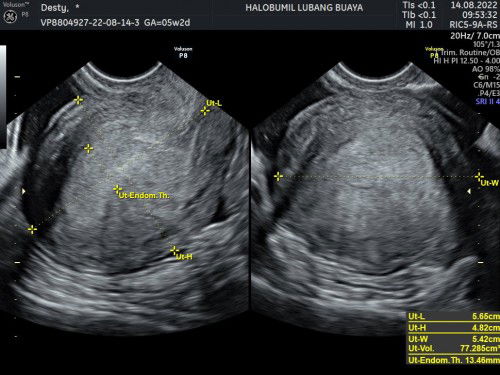

Hpht saya tanggal 8 juli, tanggal 11 agus saya tespek hasilnya garis 2 dan tanggal 14 agustus saya usg tv tp kata dokter baru penebalan dinding rahim 2 minggu lg disuruh balik lagi, apakah ada yg sama ? Boleh sharing dong pengalamannya dan ada yg paham baca hasil usg ini ga?